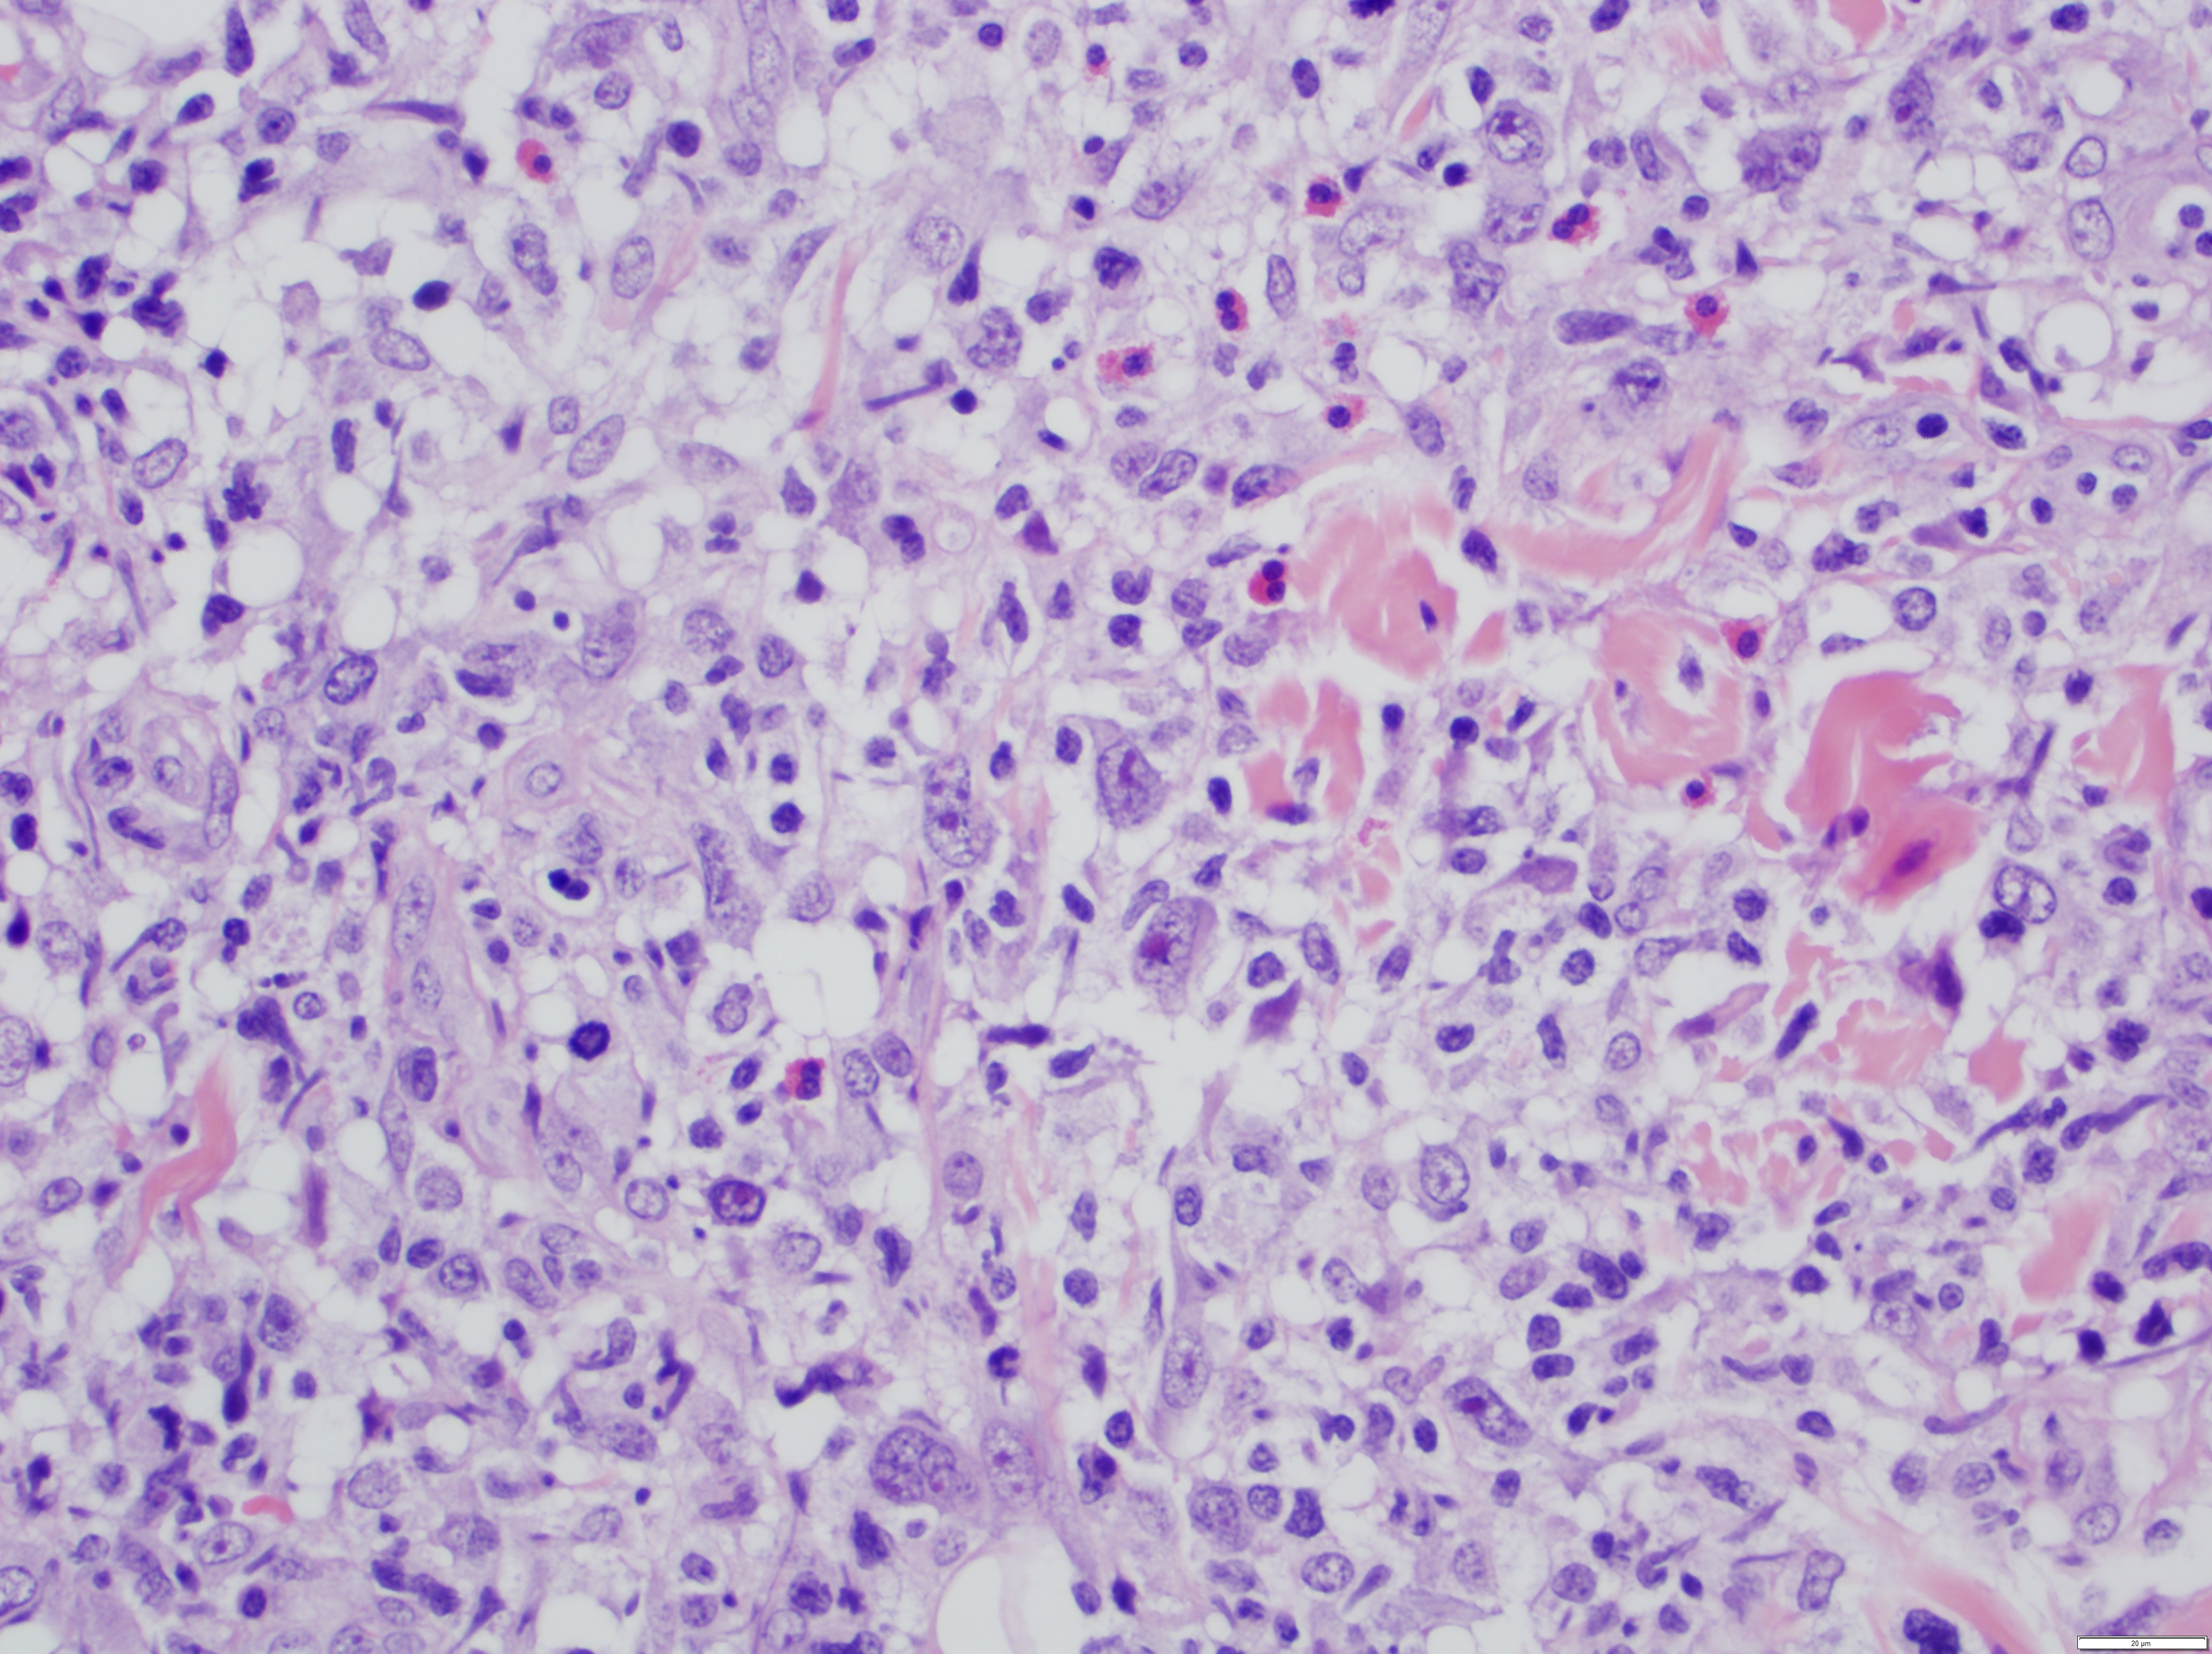

- The most characteristic appearance is the presence of few to numerous large cells with a Hodgkin or Hodgkin-Reed Sternberg admixed with a reactive background of small lymphocytes and less frequently eosinophils, plasma cells and histiocytes

- The microscopic appearance and immunophenotype of large cells is variable and led to subclassification of lymphomatoid papulosis into different categories (J Am Acad Dermatol 2016;74:59, Blood 2019;133:1703, Semin Diagn Pathol 2017;34:22, J Am Acad Dermatol 2013;68:809, J Am Acad Dermatol 2012;66:928, Am J Clin Pathol 2003;119:731, Am J Surg Pathol 2010;34:1168, Am J Surg Pathol 2013;37:1)

- Type A: wedge shaped and extensive lymphoid infiltrate with neutrophils, eosinophils and histiocytes; CD30+ cells are scattered and the overall histologic appearance mimics classic Hodgkin lymphoma

- Type C: sheets of large cells, uniformly positive for CD30, with or without epidermotropism and few admixed inflammatory cells; the lesion mimics primary cutaneous anaplastic large cell lymphoma

Microscopic (histologic) images

Contributed by Roberto N. Miranda, M.D.